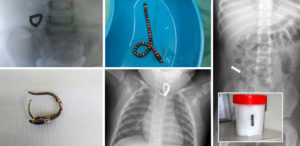

О том, что глотают люди, можно писать целые книги. Врачи-хирурги собирают целые коллекции рентгеновских снимков, на которых отображены удивительные вещи, проглатываемые человеком.

Глотают люди что угодно: кости, иголки, батарейки, саморезы, магнитные шарики, монеты, стоматологические съемные протезы. Все инородные тела делят на агрессивные и неагрессивные. При проглатывании агрессивных тел они должны быть удалены как можно быстрее. В то время как более-менее безопасные вещи могут выйти самостоятельно.

Всем пациентам при проглатывании костей делают рентген. По возможности кость сразу же удаляют эндоскопическим методом. В пищевод вводится трубка с камерой и инструментарием, при помощи которого извлекается инородное тело.

При проглатывании или вдыхании какой-либо части брекет-систем необходимо сразу же обратиться к специалисту. Особенно это касается дуги. Врач проводит визуальный осмотр. При необходимости назначается УЗИ органов брюшной полости или легких.

После установления местонахождения проглоченной части и определения угрозы для здоровья, специалист предпринимает действия по ее извлечению, только если это необходимо.

Возможные действия врача:

- Если частички застряли в легких – используется бронхоскоп;

- Если часть дуги застряла в пищеводе – специальные щипцы или эндоскоп;

- Если часть дуги впилась в слизистую желудка – требуется оперативное вмешательство.